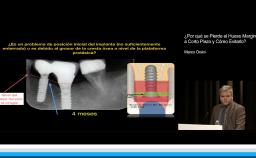

La periimplantitis constituye uno de los grandes retos a los que se enfrenta el profesional en cuya actividad diaria se incluye la colocación de implantes. Esta conferencia comienza con una introducción de aquellos aspectos que pueden interesar al clínico acerca de esta patología tales como el concepto, su prevalencia y los factores de riesgo que pueden contribuir a la aparición de este problema, mediante una revisión de la literatura de forma clara y concisa. El punto central de la conferencia lo constituye el manejo clínico de esta complicación. Se revisan tanto el tratamiento no quirúrgico como el quirúrgico, en sus diferentes modalidades y combinaciones, sus objetivos, su secuencia, los resultados que se pueden esperar obtener, y por último, los “pros” y “contras” de cada uno de ellos. Todo ello sin olvidar de que a día de hoy el mejor arma de la que disponemos frente a este problema es sin duda, la prevención mediante el establecimiento de un programa de mantenimiento adecuado.